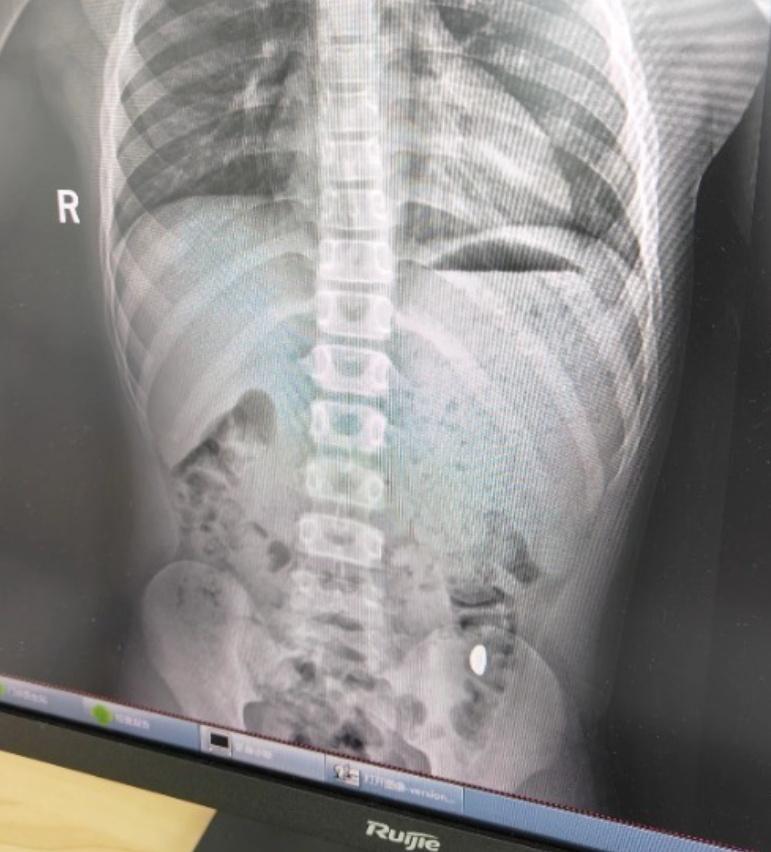

(三)医院处理:拍片定位 + 自然排泄,医生提醒 “别存侥幸”纪女士带着儿子来到了昆山市第五人民医院。医生在了解了事情的来龙去脉后,迅速为孩子安排了检查。诊断结果显示,胃内异物(10 克黄金)清晰可见,就像一个不速之客,安静地待在孩子的胃里。好在孩子在这期间并没有出现腹痛、呕吐等不适症状,这也让纪女士稍稍安心了一些。

医生表示,虽然黄金的化学性质稳定,一般不会与人体发生化学反应,对身体不会造成直接的化学伤害。但是,这颗 10 克的金豆子体积较大,在人体的消化道内属于 “大块头”,很有可能会在肠道的某些狭窄部位滞留,从而引发肠梗阻等严重问题。医生严肃地提醒纪女士,在发现孩子误吞异物后,千万不能盲目等待异物自行排泄,第一时间就医才是正确的选择。因为医生可以通过专业的检查手段,如拍片、B 超等,准确判断异物的位置和情况,从而制定出最合适的治疗方案。如果一味地心存侥幸,等待异物自行排出,很可能会错过最佳的治疗时机,导致更严重的后果。

家长发现后,心急如焚,立刻带他前往苏州大学附属儿童医院急诊科就诊。经 X 片检查,医生发现一枚密度极高的金属物体滞留于其消化道内,诊断为 “消化道异物”。由于金条体积较大,存在肠道梗阻及黏膜损伤等风险,急诊医生当即将小钱收治普外科。入院后,医生先采用保守治疗,给予促排便药物,希望金条能自行排出。然而,经过两天的动态观察,金条仍未能自然排出,再次复查 X 片发现该异物位置没有任何改变,可能已经固定或者嵌顿在肠道内,小钱随时面临着梗阻及穿孔的风险。